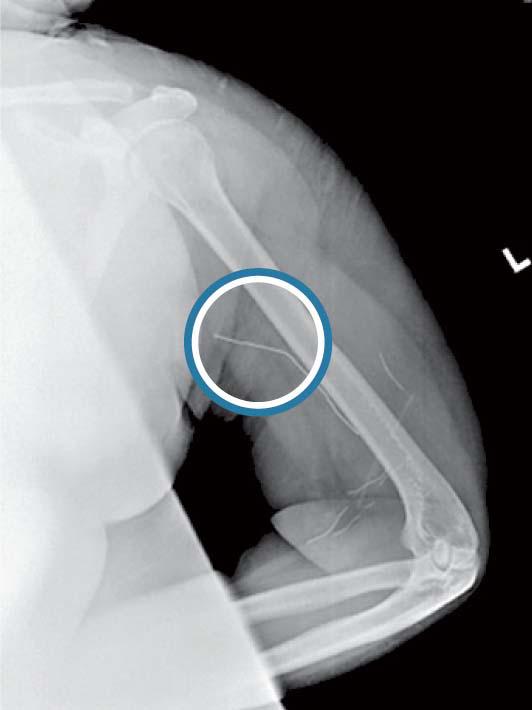

美國醫院自2005年起發現了10個自嵌個案,自插的1男9女年齡介乎15至18歲,他們嘗試將針、釘書釘、萬字夾、小石、玻璃甚至蠟筆,插入自己的手、腳、足踝和頸部。

專家稱這些超乎普通自殘的行為為自插失調症。患者有嚴重精神問題,包括抑鬱症。有患者曾遭性侵犯,有的覺得沒人關心自己,有的想過自殺,希望藉着將物件插入自己的身體內發洩不滿,尋求慰藉。